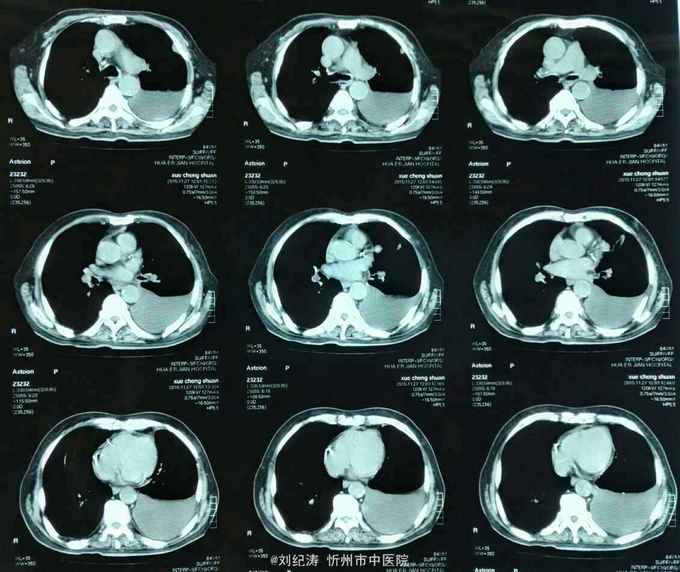

查体:ECOG评分:3分,生命指征平稳,浅表淋巴结未触及明显肿大,双眼睑无水肿,唇无发绀,颈软,双侧胸廓对称,左肺语颤增强,左肺呼吸音消失,右肺呼吸音粗,可闻及哮鸣音,心律齐,腹平软,肝脾肋下未触及,移动性浊音阴性,肠鸣音3次/分,双下肢无水肿。 辅助检查:血常规(2016.1.1):WBC:10.6*109/L,RBC:4.69*1012/L, PLT:165*109/L ,HGB:167g/L.生化(2016.1.1):谷丙转氨酶11U/L,谷草转氨酶11U/L,总蛋白60g/L,白蛋白33g/L,尿素:9.8mmol/L,肌酐:123umol/L,尿酸:251 umol/L,血糖:7.37 mmol/L;电解质:钾:4.79mmol/L,钠:123.5 mmol/L,氯:85.7 mmol/L,钙:2.03 mmol/L。肺部CT(2016.1.1):左肺完全萎缩,左侧胸腔大量积液,右肺未见异常,纵膈轻度右移,未见明显肿大淋巴结。